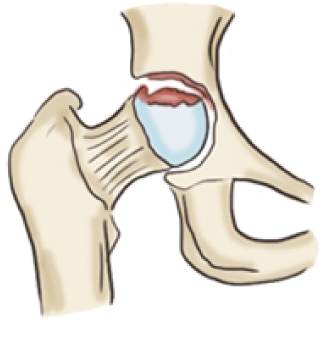

대퇴 골두 무혈성 괴사란

대퇴 골두는 관골과 맞닿아 있는 둥근 부분으로 고관절의 머리 부분을 말합니다.

대퇴골두에 혈류가 차단되면 뼈조직이 죽는 괴사가 일어나는데 이를 '대퇴 골두 무혈성 괴사'라고 진단합니다.

흔히 뼈가 썩는다라고 알고 있는데 뼈가 썩는 것이 아닌 조직이 죽어 골절되거나 무너져 내리기 쉬운 상태를 뜻합니다.